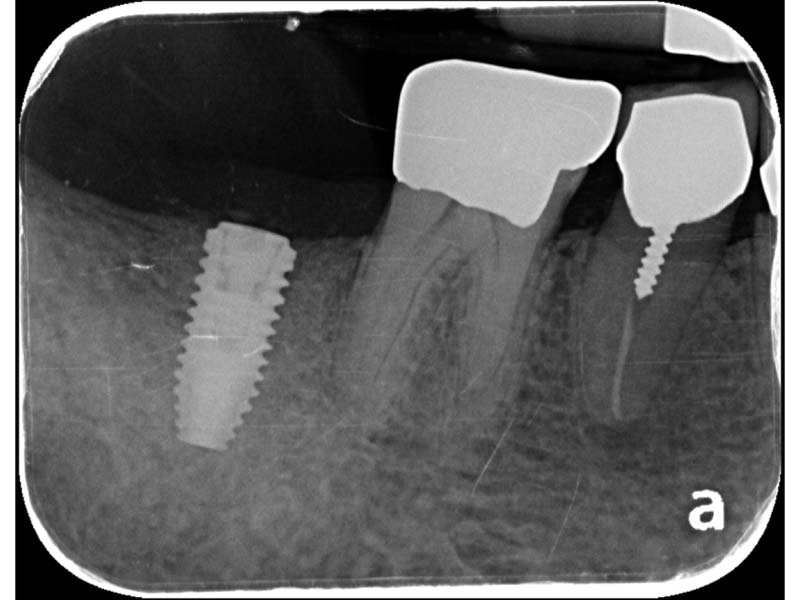

圖例為案例分享:

術前

植牙術後5.5個月

帳棚釘+骨粉+再生膜術後7個月

植牙當日